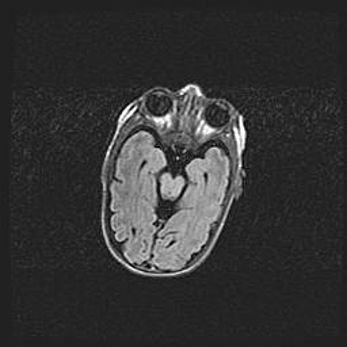

Множественные кисты обоих полушарий головного мозга, наибольшая из них в правой затылочной области. Ассиметричная атрофическая гидроцефалия.

Возраст: 7 месяцев

Вес: 5660 г

Пол: мужской

Окружность головы: 41,5 см

Срок гестации: 28-29 недель

Кисты головного мозга развиваются в результате многоочаговых некрозов вещества мозга и возникают вследствие перенесенной перинатальной инфекции, менингитов, энцефалитов, асфиксии, родовой травмы, расстройств мозгового кровообращения различного генеза. Образованию кист в веществе головного мозга плодов и новорожденных способствуют такие факторы, как высокое содержание в нем воды, недостаточная (или отсутствие) миелинизация и слабая астроглиальная реакция на повреждение.

Кисты могут сочетаться с гидроцефалией и другими поражениями головного мозга.